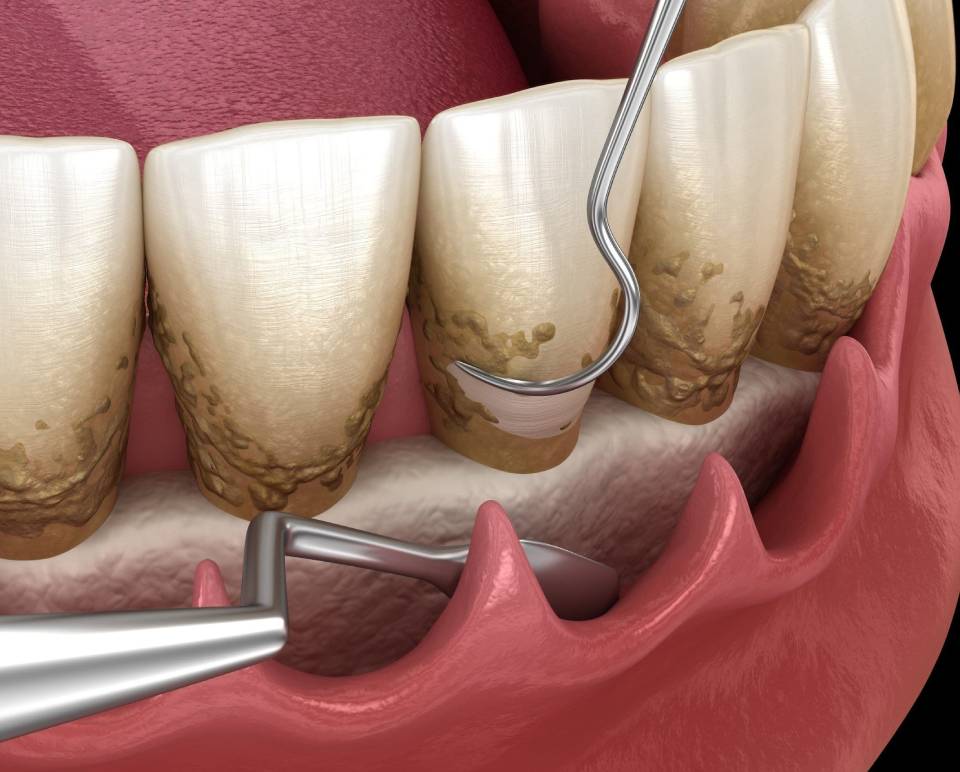

Gum Treatment

At Smile Dental Clinic and Implant Centre, we provide specialized gum treatments to address issues like gum disease, inflammation, and receding gums. Our goal is to restore gum health, prevent tooth loss, and maintain a healthy smile.

Scaling And Polishing

Flap Surgery